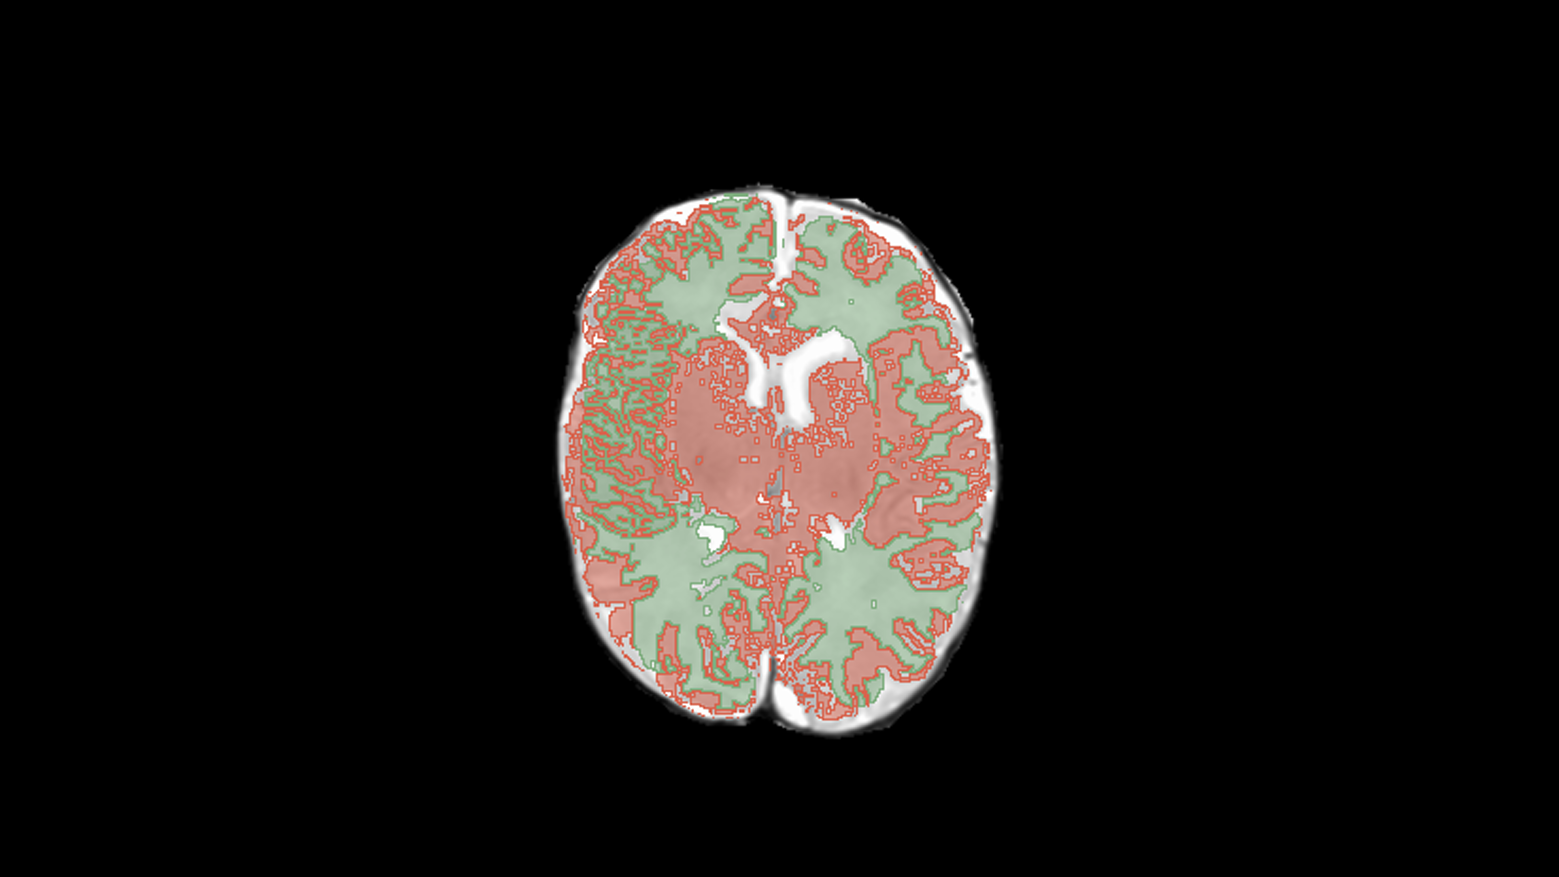

Пример работы алгоритма:

Решение автоматически определяет на каждом срезе МРТ, где находится серое и белое вещество, с определённой долей вероятности.

Сервис в первую очередь морфометрический, измеряющий объёмы. После обработки пользователь видит предсказанный моделью объём серого и белого вещества и цереброспинальной жидкости (ЦСЖ), а также описание крупнейших структур.

Из таблицы можно перейти в само исследование, где уже выделены маски белого и серого вещества: